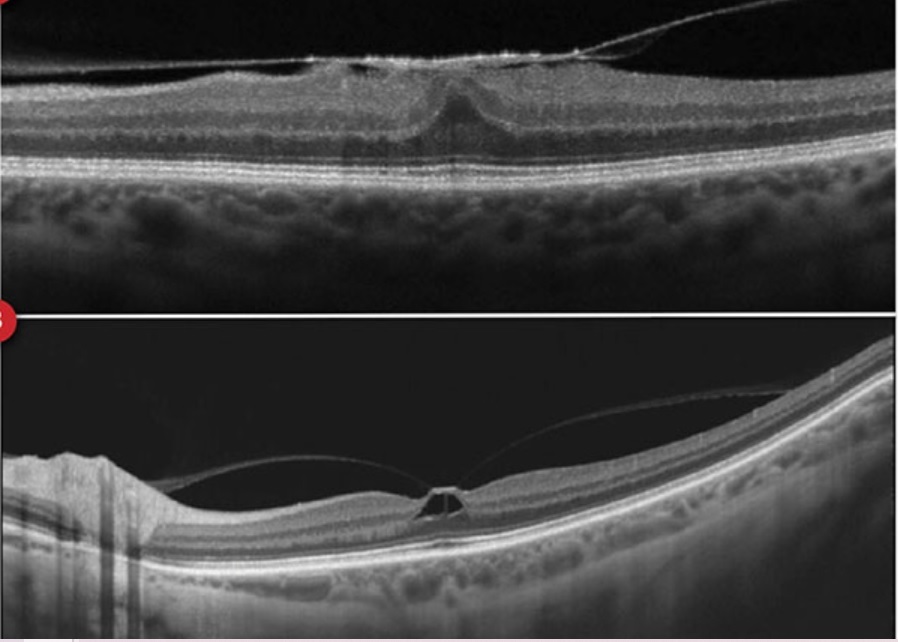

O que é o Pseudo-buraco de Mácula?

Distorção da região foveal, causada por uma MER, que gera impressão de um Buraco de Mácula, porém, sem acometer a espessura total da retina.

Estágio 1: Buraco macular iminente

- 1a: Pseudocisto foveal

- 1b: Descontinuidade da retina externa (até 300 micrômetros)